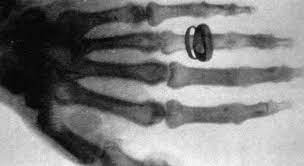

• Rajos x

Rajos x

El 8 de novembre de 1895 el físic alemany Wilhelm Conrad Roentgen va descobrir els raigs X mentre realitzava experiments amb tubs de buit i un generador elèctric.